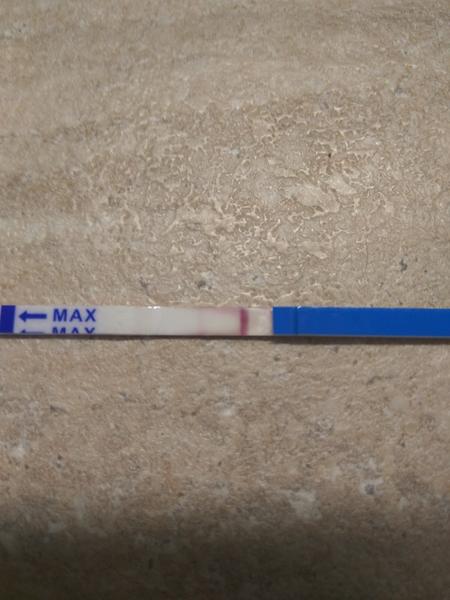

První byl ClearBlue a téměř hned tam naskočilo plus.

Tak nevim ... ☹ Dávám fotku, skuste posoudit...

- Slabá druhá čárka na domácím těhotenském testu může znamenat velmi časné těhotenství, biochemické těhotenství nebo vliv ředění moči a různou citlivost testů; spolehlivější potvrzení poskytne opakované testování z první ranní moči a krevní odběr hCG.

- V diskuzi byly zmíněny konkrétní citlivosti testů (ClearBlue 25 mIU/ml, ForYou 20 mIU/ml, RapidClear 10 mIU/ml) a zároveň varování, že intenzita čárky závisí na značce, množství barviva v testu a koncentraci moči, takže srovnávání čárek mezi různými testy je nespolehlivé.

A: Intenzita čárky závisí na koncentraci moči (nejkoncentrovanější je ranní moč), na množství barviva v konkrétním testu a na množství hCG v krvi; v diskuzi také zaznělo, že čárka může být slabá v časném těhotenství nebo při biochemickém těhotenství.

- Význam velmi slabé čárky: část diskuzí považovala slabou čárku za znamení časného těhotenství, jiní upozorňovali na možnost biochemického těhotenství nebo technické artefakty.